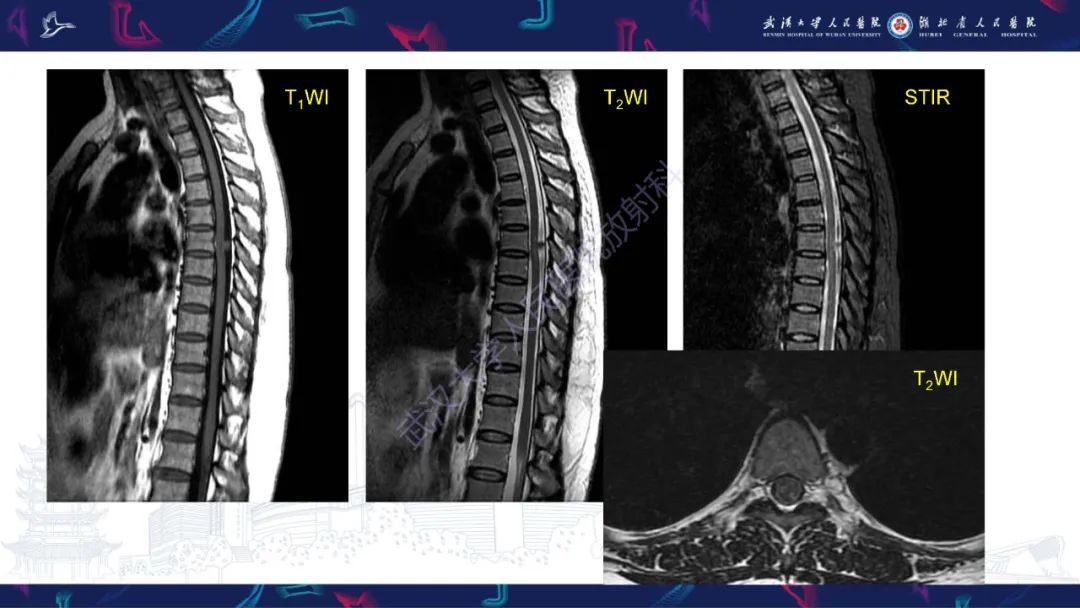

【PPT】椎管内孤立性纤维瘤/血管外皮细胞瘤影像诊断-2